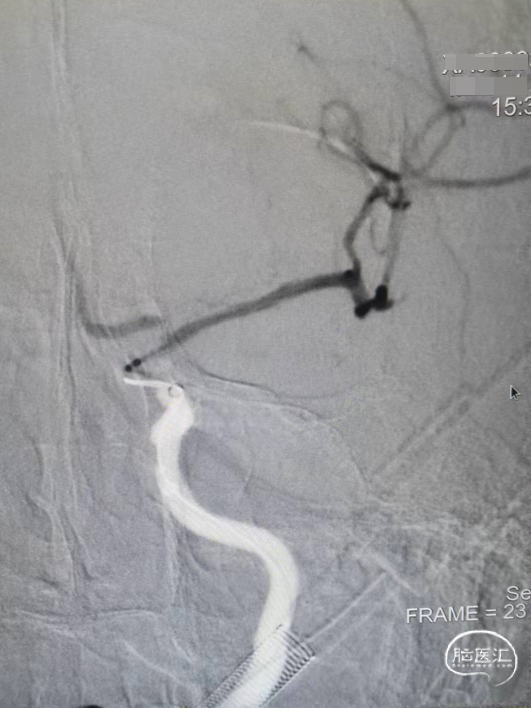

造影显示左侧的颈内动脉末端闭塞,中间导管造影显示大脑前和大脑中动脉显影,明确颈内末端闭塞。

中间导管到位之后送入RECO取栓支架 6*30cm、微导管,调整好微导管位置之后释放RECO取栓支架 6*30cm,支架展开之后血管血流通畅。

先负压抽吸,然后释放RECO取栓支架 6*30cm在负压下进行取栓操作。